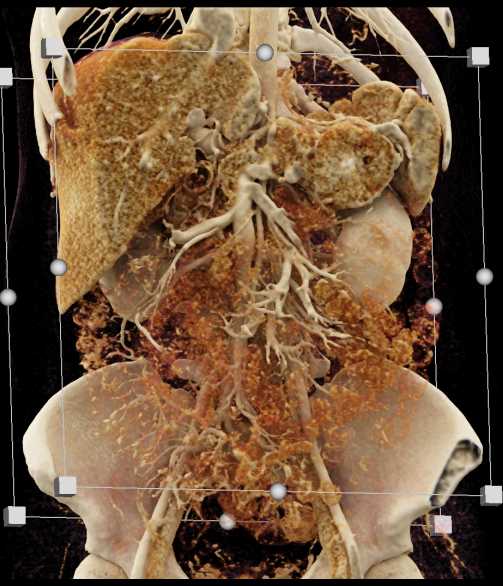

Neuroendocrine Tumor Pancreas